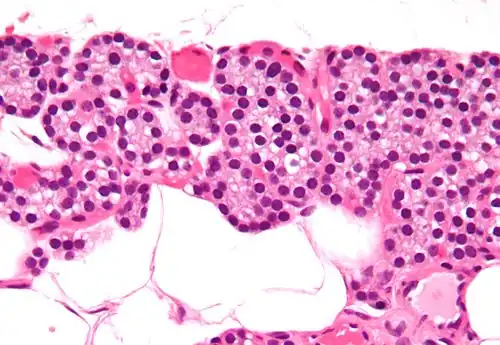

Célula principal paratiroidea

Las células principales paratiroideas (o simplemente células paratiroideas) son aquellas células encargadas de producir la hormona paratiroidea o parathormona (PTH). Forman, junto a las células oxifílicas, las glándulas paratiroides ubicadas en el cuello.